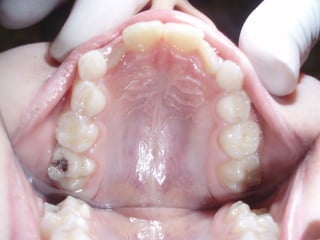

   Οι μασητικές επιφάνειες των οπισθίων δοντιών

ευνοούν την κατακράτηση τροφών και μικροβίων και

συχνά τερηδονίζονται αμέσως μετά την ανατολή τους.

   Έρευνα της Ελληνικής Οδοντιατρικής Ομοσπονδίας

έδειξε ότι σε παιδιά ηλικίας 12 ετών το 83% των

τερηδονισμένων επιφανειών παρατηρείται στις

μασητικές επιφάνειες      (Ουλής Κ.Ι. συν. Ελληνικά

Στοματολογικά Χρονικά 2009’ 53(3)΄97-120)

   Επίσης και μετά από παρακολούθηση έως 10 - 15 έτη, μόνο

το 30 -40% των δοντιών με κάλυψη είχαν μασητικές

αποκαταστάσεις, σε σχέση με 60 -80% των δοντιών χωρίς

καλύψεις.

   Μελέτες έχουν δείξει μείωση της τερηδόνας ,μετά την

τοποθέτηση ΚΟΣ, 85 -37 % μετά από 2 – 6 έτη

    οι προληπτικές καλύψεις θα πρέπει να εφαρμόζονται

ανάλογα με τον βαθμό κινδύνου ανάπτυξης τερηδόνας των

ατόμων, ή των επιφανειών επιλεκτικά και εξατομηκευμένα